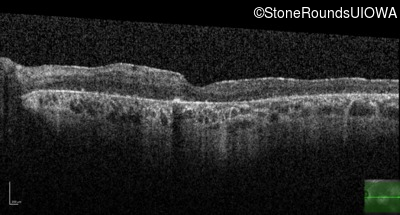

Optical Coherence Tomography - Right - 5/400

Exemplar / OCT Stack

OCT Stack